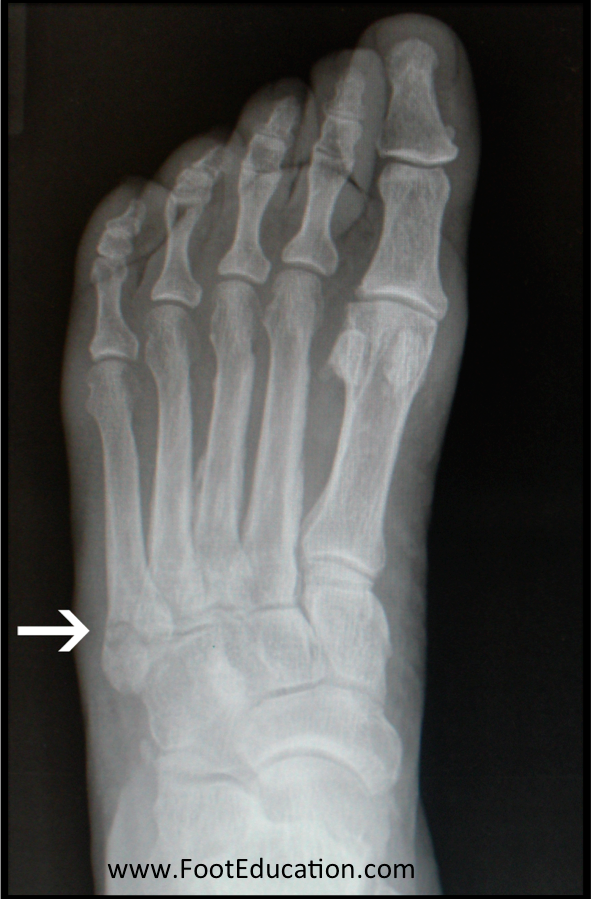

From www.footeducation.com

5th Metatarsal Avulsion Fracture FootEducation Boot For 4Th Metatarsal Fracture Metatarsal fractures are common in the paediatric population and rarely require operative management. Most metatarsal fractures can be treated with an initial period of elevation and limited weight bearing. A fifth metatarsal tuberosity avulsion fracture can be treated acutely with a compressive dressing, then the patient can be transitioned to a short leg walking boot for two weeks, with. You. Boot For 4Th Metatarsal Fracture.

From footeducation.com

Metatarsal Shaft Fractures FootEducation Boot For 4Th Metatarsal Fracture Metatarsal fractures are common in the paediatric population and rarely require operative management. A fifth metatarsal tuberosity avulsion fracture can be treated acutely with a compressive dressing, then the patient can be transitioned to a short leg walking boot for two weeks, with. This is followed by gradual weight bearing, as tolerated, in a cast or walking. Most metatarsal fractures. Boot For 4Th Metatarsal Fracture.